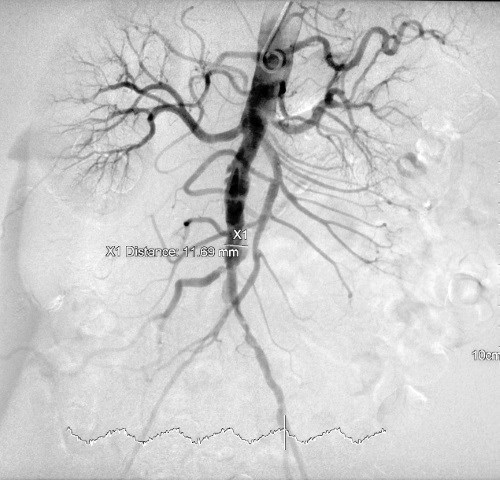

![]() ![]() Капилляры – это крошечные кровеносные сосуды. Они состоят только из слоя внутренней оболочки. Строение кровеносных сосудов Все кровеносные сосуды (кроме капилляров) имеют одинаковое базовое строение. Внешняя оболочка. Каждый сосуд покрыт наружной соединительнотканной оболочкой – внешней, или адвентициальной. Средняя оболочка. Гладкие мышцы и эластичные волокна этого слоя придают сосуду подвижность и эластичность. Внутренняя оболочка. Состоит из одного гладкого слоя сплющенных эндотелиальных клеток. Просвет сосуда. Это пространство в центре, по которому течет кровь. Артериальная система Название «артерия» происходит от греческого слова arteria, что означает «несущая воздух». Древние греки выбрали это название неспроста: они считали, что артерии переносят только воздух. Такое мнение было основано на их наблюдениях о том, что после смерти в артериях не остается крови. А это, как нам теперь известно, происходит из-за того, что после остановки сердца кровь скапливается в венах. ![]() Кровеносные сосуды можно увидеть с помощью специального типа рентгеновских лучей. Такой снимок называют ангиограммой. Артерии действительно переносят воздух, которым мы дышим, но не в буквальном смысле. Все артерии, кроме легочной, переносят обогащенную кислородом кровь от сердца. Легочная артерия, наоборот, переносит ненасыщенную кислородом кровь из сердца в легкие, где она обогащается кислородом и возвращается обратно. Аорта. Все артерии берут начало из двух источников: аорты и легочной артерии. Диаметр аорты, самой крупной артерии в организме, равен диаметру садового шланга. Аорта начинается от левого желудочка. Выходя из желудочка, она образует дугу, от которой ответвляются другие артерии, питающие различные структуры головы и рук. Затем аорта совершает изгиб в форме перевернутой буквы U и идет по направлению к груди, животу и нижним конечностям, параллельно ветвясь на другие артерии. Коронарные артерии. Перед тем как совершить свой U-образный изгиб, аорта должна насытить сердце кровью – через коронарные артерии, которые ветвятся на сеть мелких сосудов. Сердце нуждается в собственном кровоснабжении, ведь миокард и перикард слишком удалены от эндокарда и потому не могут получать через кровь нужные питательные вещества. ![]() Артериальную систему кровообращения образуют две главные артерии: аорта и легочный ствол, – которые выходят напрямую из сердца. Легочные артерии. Легочные артерии, снабжающие легкие кровью, значительно короче своих партнеров по системе. Они выходят из основания правого желудочка, а затем разделяются на правую и левую ветви. Артериолы. Артериолы – это самые маленькие артерии во всей артериальной системе. Из них образуются капилляры. Артериолы направляют кровоток к капиллярной сети, используя для этого тонкие пучки кольцевых гладкомышечных волокон – прекапиллярных сфинктеров. По команде мозга эти мышечные кольца сокращаются, уменьшая диаметр артериол и приток крови к капиллярам. По этой причине артериолы иногда называют прекапиллярными резистивными сосудами. Венозная система Самые маленькие вены – это венулы. Они выходят из капиллярного русла и сливаются в более крупные вены, у части которых есть специальные заслонки на стенках – венозные клапаны. В промежутках между сердечными сокращениями давление в организме падает, и кровь начинает течь в обратном направлении. Чтобы предотвратить обратный кровоток, венозные клапаны закрываются. По сравнению с артериями у вен более широкий просвет и тонкие стенки, образованные гладкими мышцами и менее эластичной тканью. К тому моменту, когда кровь попадает в венозное русло, давление сердца на артерии рассеивается. Поэтому стенки вен значительно тоньше. Два круга кровообращения В нашем теле есть два обособленных, но взаимосвязанных круга кровообращения. Большой круг кровообращения перекачивает обогащенную кислородом кровь из левого желудочка через аорту во все части тела (кроме легких). У легких есть собственное легочное кровообращение. Необогащенная кислородом кровь из тканей идет по полым венам и поступает в правое предсердие. Затем она попадает в правый желудочек, а после доставляется в легкие. Там она избавляется от углекислого газа, насыщается кислородом и доставляется по легочным венам в левое предсердие. Далее она проходит в левый желудочек, и весь цикл повторяется. ![]() Везде, где есть артерия, найдется и вена, которая будет переносить ненасыщенную кислородом кровь обратно в сердце. Вены из головы, рук и шеи сходятся в верхней полой вене, а вены, отводящие кровь от туловища и нижних конечностей, сливаются в нижней полой вене. Обе эти вены открываются в правое предсердие. Туда же входит и венечный (коронарный) синус – особая структура, образованная слиянием коронарных вен, которые отвечают за отток необогащенной кислородом крови из сердца. Выводящие кровь из легких вены объединяются в легочную вену, которая, в отличие от остальных вен, доставляет обогащенную кислородом кровь в левое предсердие. ![]() В венах скапливается около 60 % общего объема крови. Перед тем как попасть в сердце, все они сливаются в полую или легочную вену. Красные штучки Британский историк и биограф Роберт Лейси в своей книге «Аристократы» рассказывает, что именно испанцы породили в мировом сознании мысль о голубой крови аристократов. Эта идея возвращает нас к эпохе Средневековья в Европе, когда социальный класс человека определяли по тому, насколько заметными были синие вены под его кожей. Кожа у привилегированных особ была бледной, поэтому их поверхностные вены были заметнее, чем у загорелых крестьян, которые проводили свою жизнь в полях. Вены бледнокожих людей кажутся синими из-за физики электромагнитного излучения. А точнее – из-за того, как ведут себя различные длины волн света при проникновении под кожу. Красный и оранжевый световые спектры имеют большую длину волны, поэтому кожа и гемоглобин в крови абсорбируют их. У синего длина волны короче, поэтому он не может проникнуть глубоко под кожу, а вместо этого отражается от нее, позволяя вам увидеть синеву. |